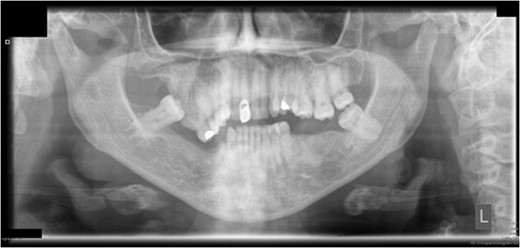

Preoperative orthopantomograph showing expansion of the right maxillary tuberosity.

Craniofacial dysplasias may represent areas of anatomical variation where the blood supply may be susceptible to disruption. Although the patient had a biopsy showing normal bone, the maxillary tuberosity was expanded and hyperplastic clinically. This in itself would not however have accounted for the degree of avascularity seen in this case.